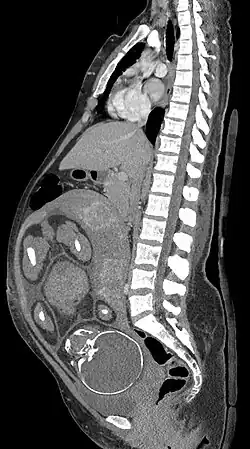

Exames de imagem na gravidez

Exames de imagem na gravidez podem ser indicados por causa de complicações da gravidez, doenças intercorrentes ou como parte da assistência pré-natal.

Ressonância magnética

A ressonância magnética (RM), sem meio de contraste em RM, não está associada a riscos para a mãe ou o feto e, juntamente com a ultrassonografia médica, é a técnica de escolha para exames de imagem na gravidez.[1]